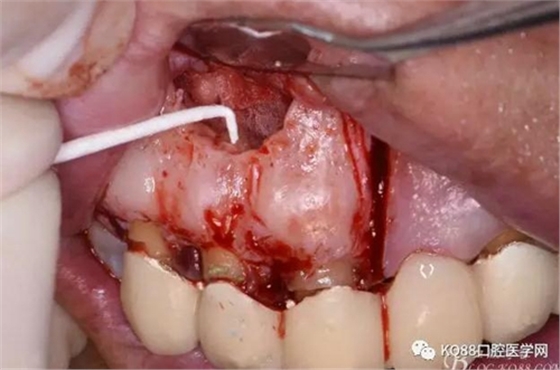

圖14.吸潮紙尖干燥根管

圖15.取愛如特生物陶瓷材料

圖16.放置在干燥好的根管內(nèi)

圖17.根尖倒充填完畢